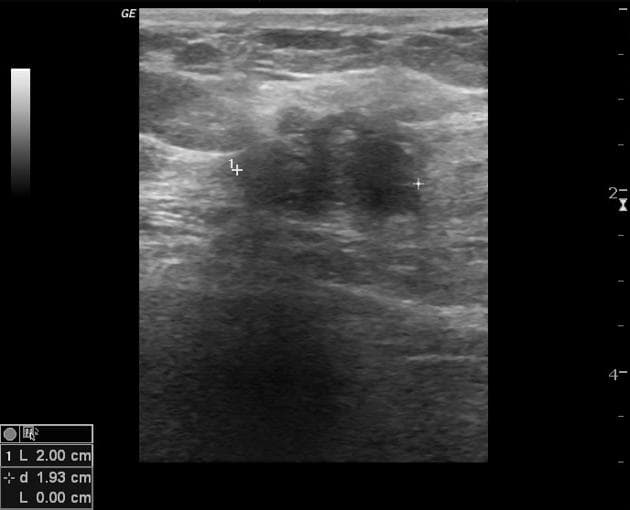

- Siêu âm cho thấy khối tổn thương hình bầu dục, giảm âm, giới hạn rõ, nằm ở vị trí nông, phía trên cơ thẳng bụng phải, làm lõm vào cơ này.

- Trên Doppler năng lượng, thấy một lượng nhỏ tín hiệu lưu thông ở vùng ngoại vi của khối tổn thương.

- "Siêu âm thường cho thấy khối tổn thương rắn, giảm âm, giới hạn rõ ở thành bụng; cộng hưởng từ (MRI) có thể được dùng để đánh giá chi tiết hơn nếu cần."